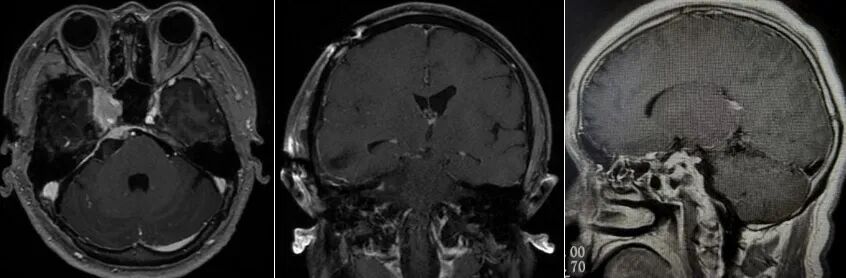

患者术后MRI

由于肿瘤侵入海绵窦,为了避免术后造成患者眼睑下垂、眼球运动受限、视力障碍等严重的颅神经损伤后遗症,术中残留了少许肿瘤,日后辅以放射治疗予以消除。术后,患者未出现神经功能障碍,颜面部疼痛症状也消失了。病理报告“脑膜瘤,WHO 1级,皮细胞型”。经过短期治疗后,患者顺利出院。